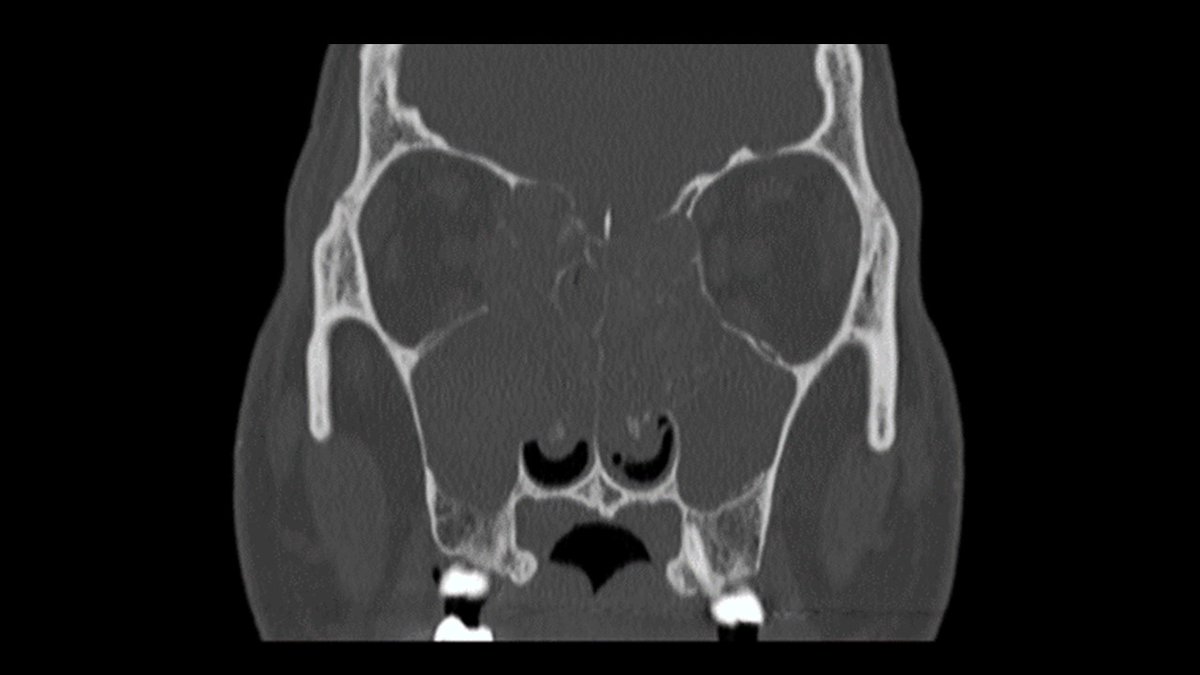

Just sharing the link to my case submission on MACS that is now available on the Cushing’s Hub website as an interactive case study. cushingshub.com/case-studies/a… @springermeded #Endotwitter